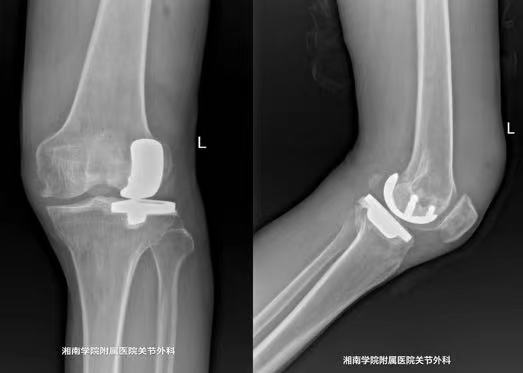

唐新文介绍,单髁置换相对于传统的全膝关节置换术更加微创,手术切口仅为原来的1/2,对患者的损伤更小,术后疗效更佳,同时,手术费用及住院时间也明显降低,极大地方便了患者。唐新文说,“单髁置换术既能解决疼痛,恢复膝关节功能,又能最大程度保留骨量和韧带,还具有创伤小、术后恢复快、并发症发生率低等优势,是目前最适合患者的治疗方案。”

在医务人员的精心安排下,手术顺利完成,术中出血少、创伤小,为患者后面的快速康复奠定了良好的基础。术后第一天,谢爷爷即可拄拐下地行走,其左膝外翻畸形也得到部分纠正。术后第二天,唐新文查看患者左膝关节功能锻炼,发现谢爷爷已经能很好的完成抬腿、屈曲等动作,疼痛感较术前也得到了明显减轻。谢爷爷满意地说“我们村还有好多腿脚不好的人,我都要推荐他们到你们这里来就医。”